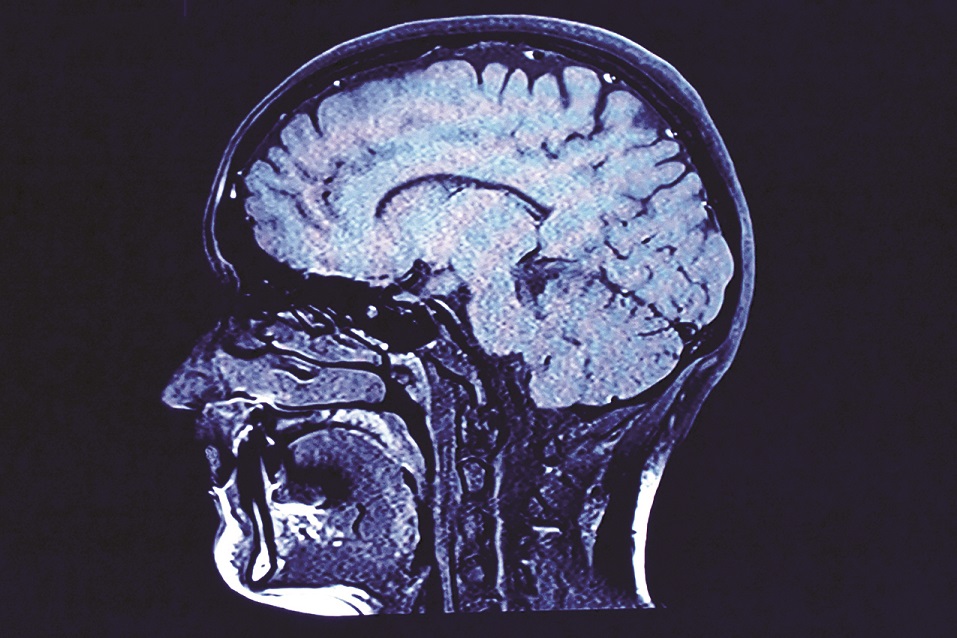

While there is usually no cure for chronic pain, with fluoroscopic guidance, Dr. Siddiqui treats and diagnoses many spinal conditions with interventional pain management techniques. Some of these techniques include epidural steroid injections, facet joint injections/medial branch blocks, radiofrequency ablation procedures/rhizotomy and neurolysis, discograms, IDET, stellate ganglion and ganglion impar blocks, epidural blood patch, spinal cord stimulation, sacroiliac joint injections, trigger point injections and neurotoxin injections (Botox). With the patient in mind, convenient on-site imaging and fluoroscopy-equipped rooms allow patients to receive their treatment at UBNS.